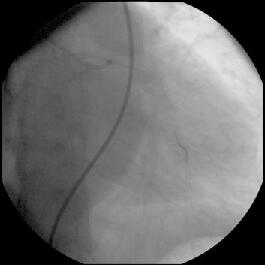

(『ChoicePT2.GW.Fracture』)、#9の末梢枝に遺残してしまいました

(『ChoicePT2.Fnl』2枚)。幸い虚血所見がまったくありませんでしたので手技は終

了とし、術後のCK逸脱もなし、翌日お元気に退院されました。